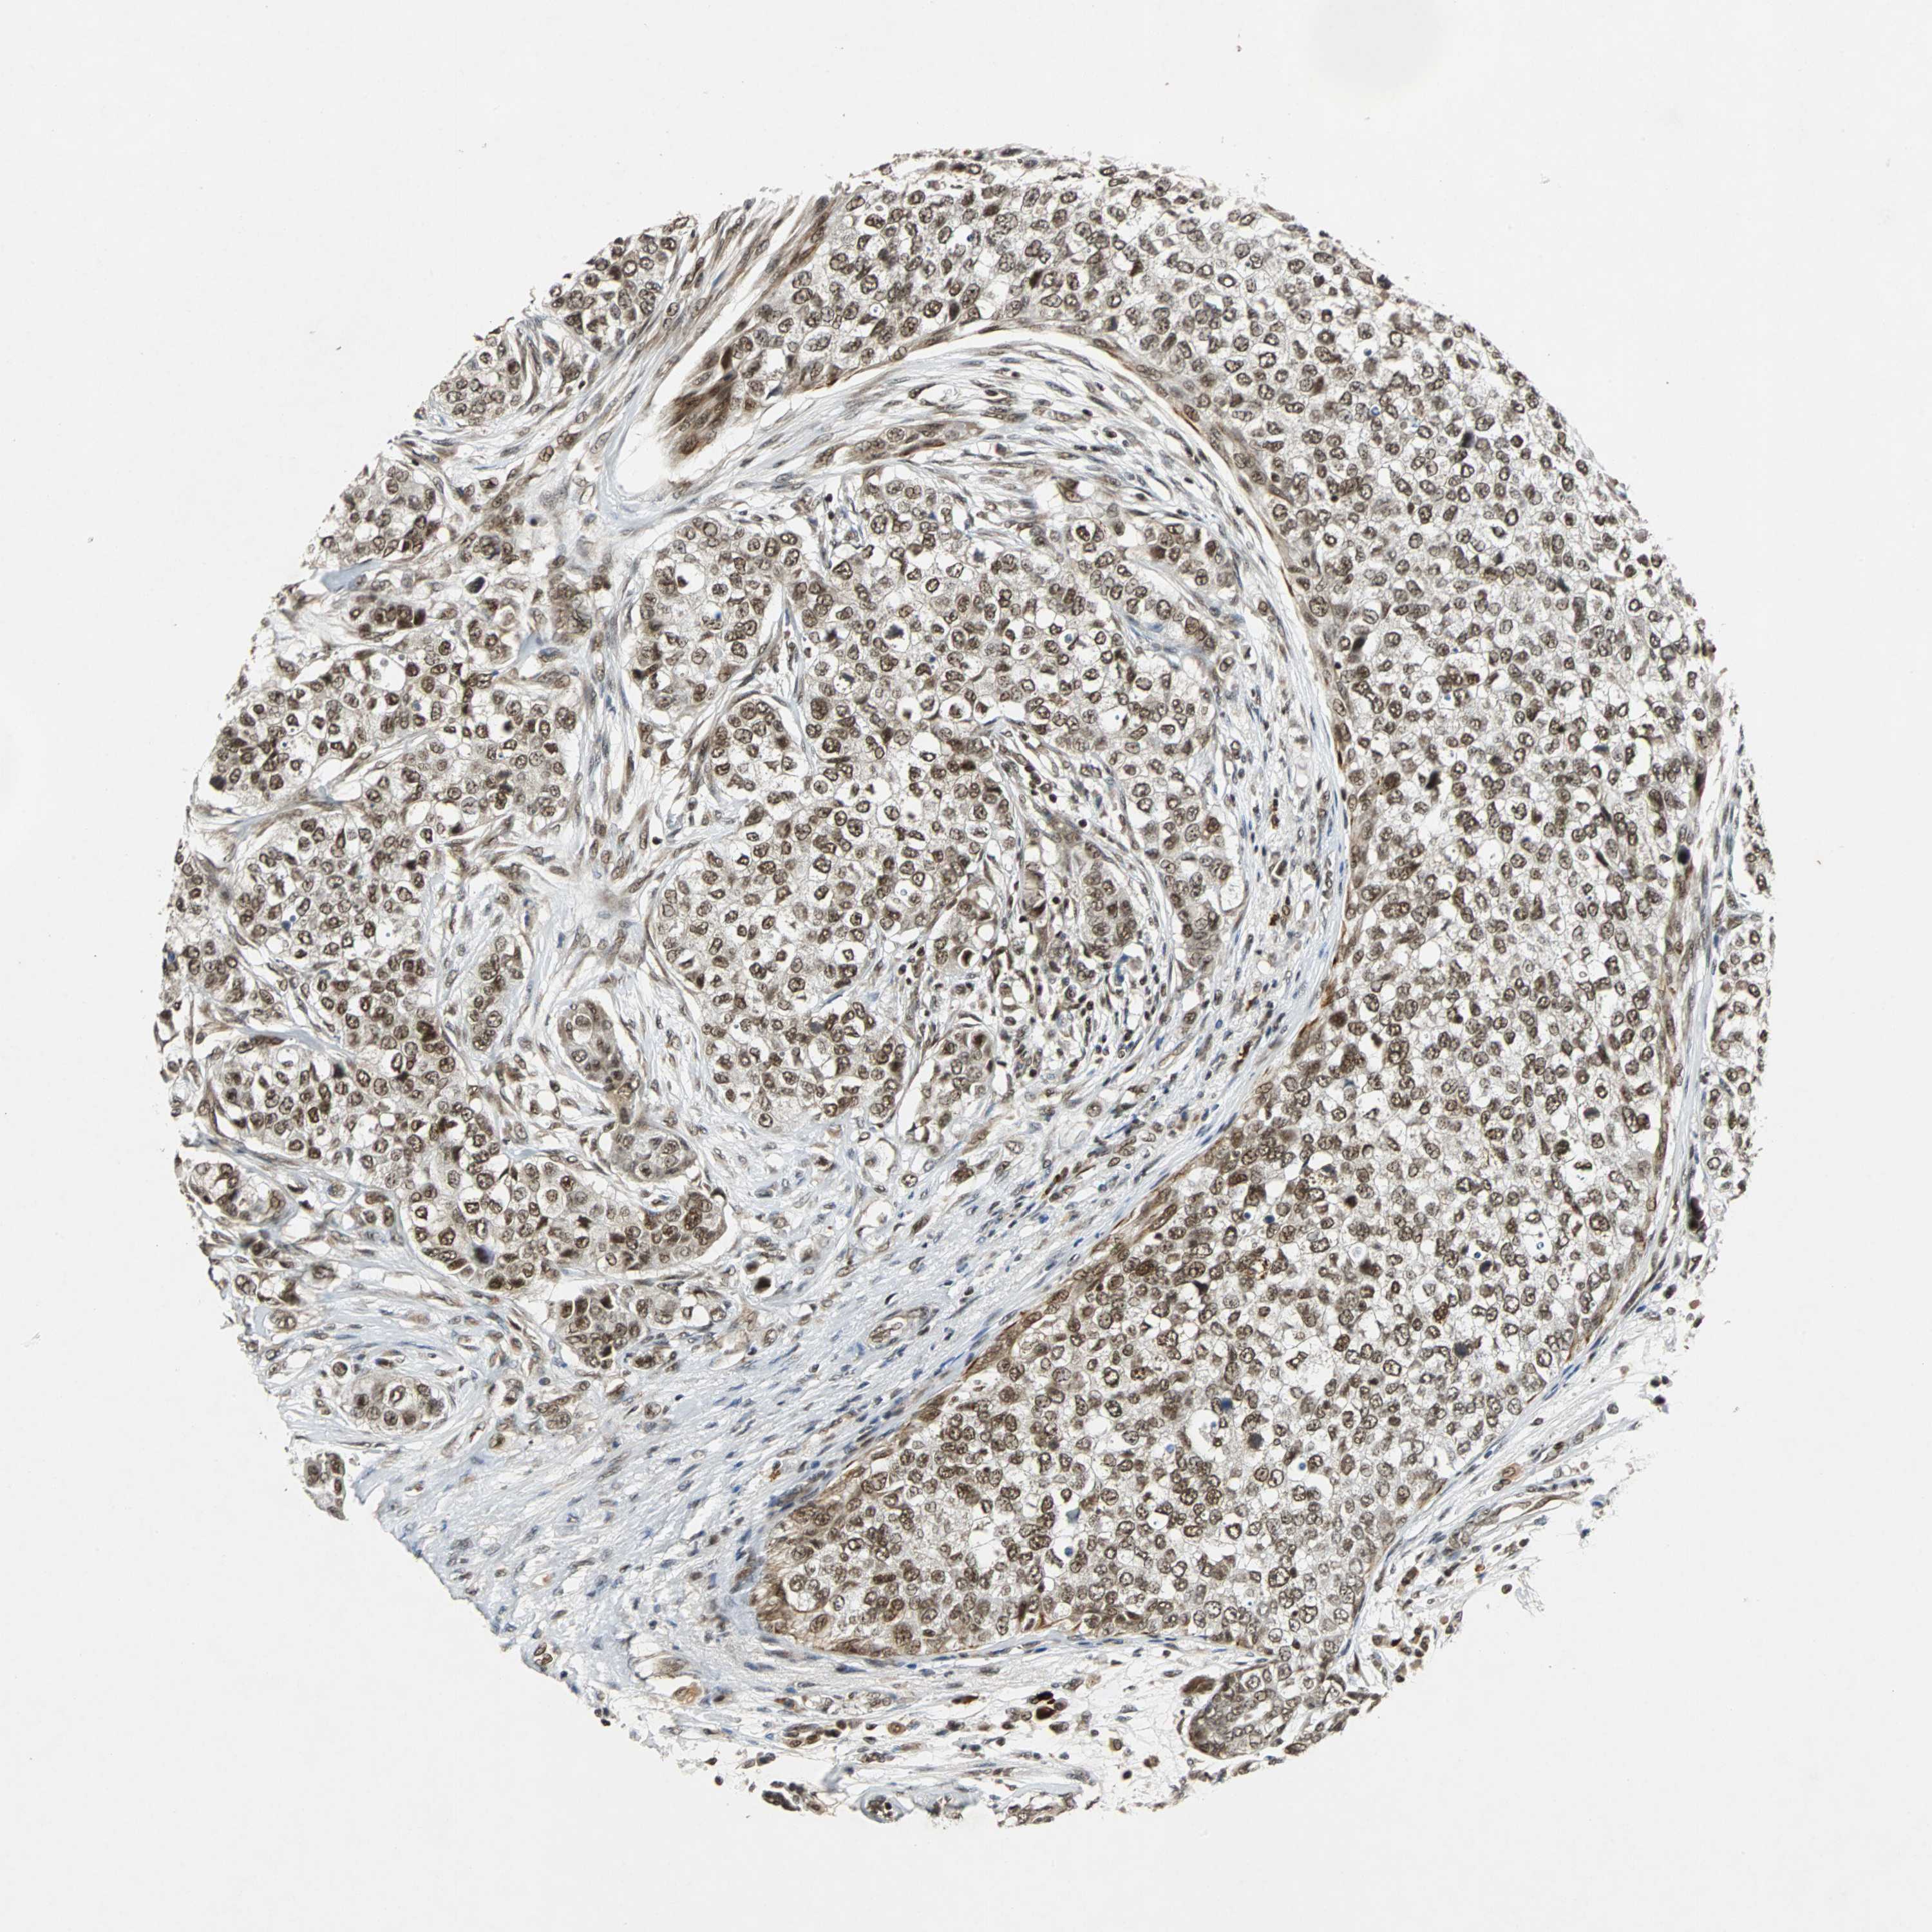

BRCA TCGA BRCA VALIDATION PROTEIN EXPRESSION

ANTIBODIES

AND

VALIDATION